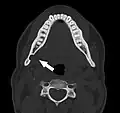

Axial computed tomograph of the same person. The Stafne defect appears as a well corticated 1 cm round defect in the medial cortex of the mandible in the right angle of the jaw (arrowed).

Stafne's defect is usually discovered by chance during routine dental radiography.[11] Radiographically, it is a well-circumscribed, monolocular, round, radiolucent defect, 1–3 cm in size, usually between the inferior alveolar nerve (IAN) and the inferior border of the posterior mandible between the molars and the angle of the jaw. It is one of the few radiolucent lesions that can occur below the IAN. The border is well corticated and it will have no effect on the surrounding structures. Computed tomography (CT) will show a shallow defect through the medial cortex of the mandible with a corticated rim and no soft tissue abnormalities, with the exception of a portion of the submandibular gland. Neoplasms, such as metastatic squamous cell carcinoma to the submandibular lymph nodes or a salivary gland tumour, could create a similar appearance but rarely have such well defined borders and can usually be palpated in the floor of the mouth or submandibular triangle of the neck as a hard mass. CT and clinical exam is typically sufficient to distinguish between this and a Stafne defect. The Stafne defect also tends to not increase in size or change in radiographic appearance over time (hence the term "static bone cyst"), and this can be used to help confirm the diagnosis.[11] Tissue biopsy is not usually indicated, but if carried out, the histopathologic appearance is usually normal salivary gland tissue. Sometimes attempted biopsy of Stafne defects reveals an empty cavity (possibly because the gland was displaced at the time of biopsy), or other contents such as blood vessels, fat, lymphoid or connective tissues. Defects of the anterior lingual mandible may require biopsy for correct diagnosis at this unusual location.[5] The radiolucent defect here may be superimposed on the lower anterior teeth and be mistaken for an odontogenic lesion. Sometimes the defect may interrupt the contour of the lower border of the mandible, and may be palpable. Sialography may be sometimes used to help demonstrate the salivary gland tissue within the bone.